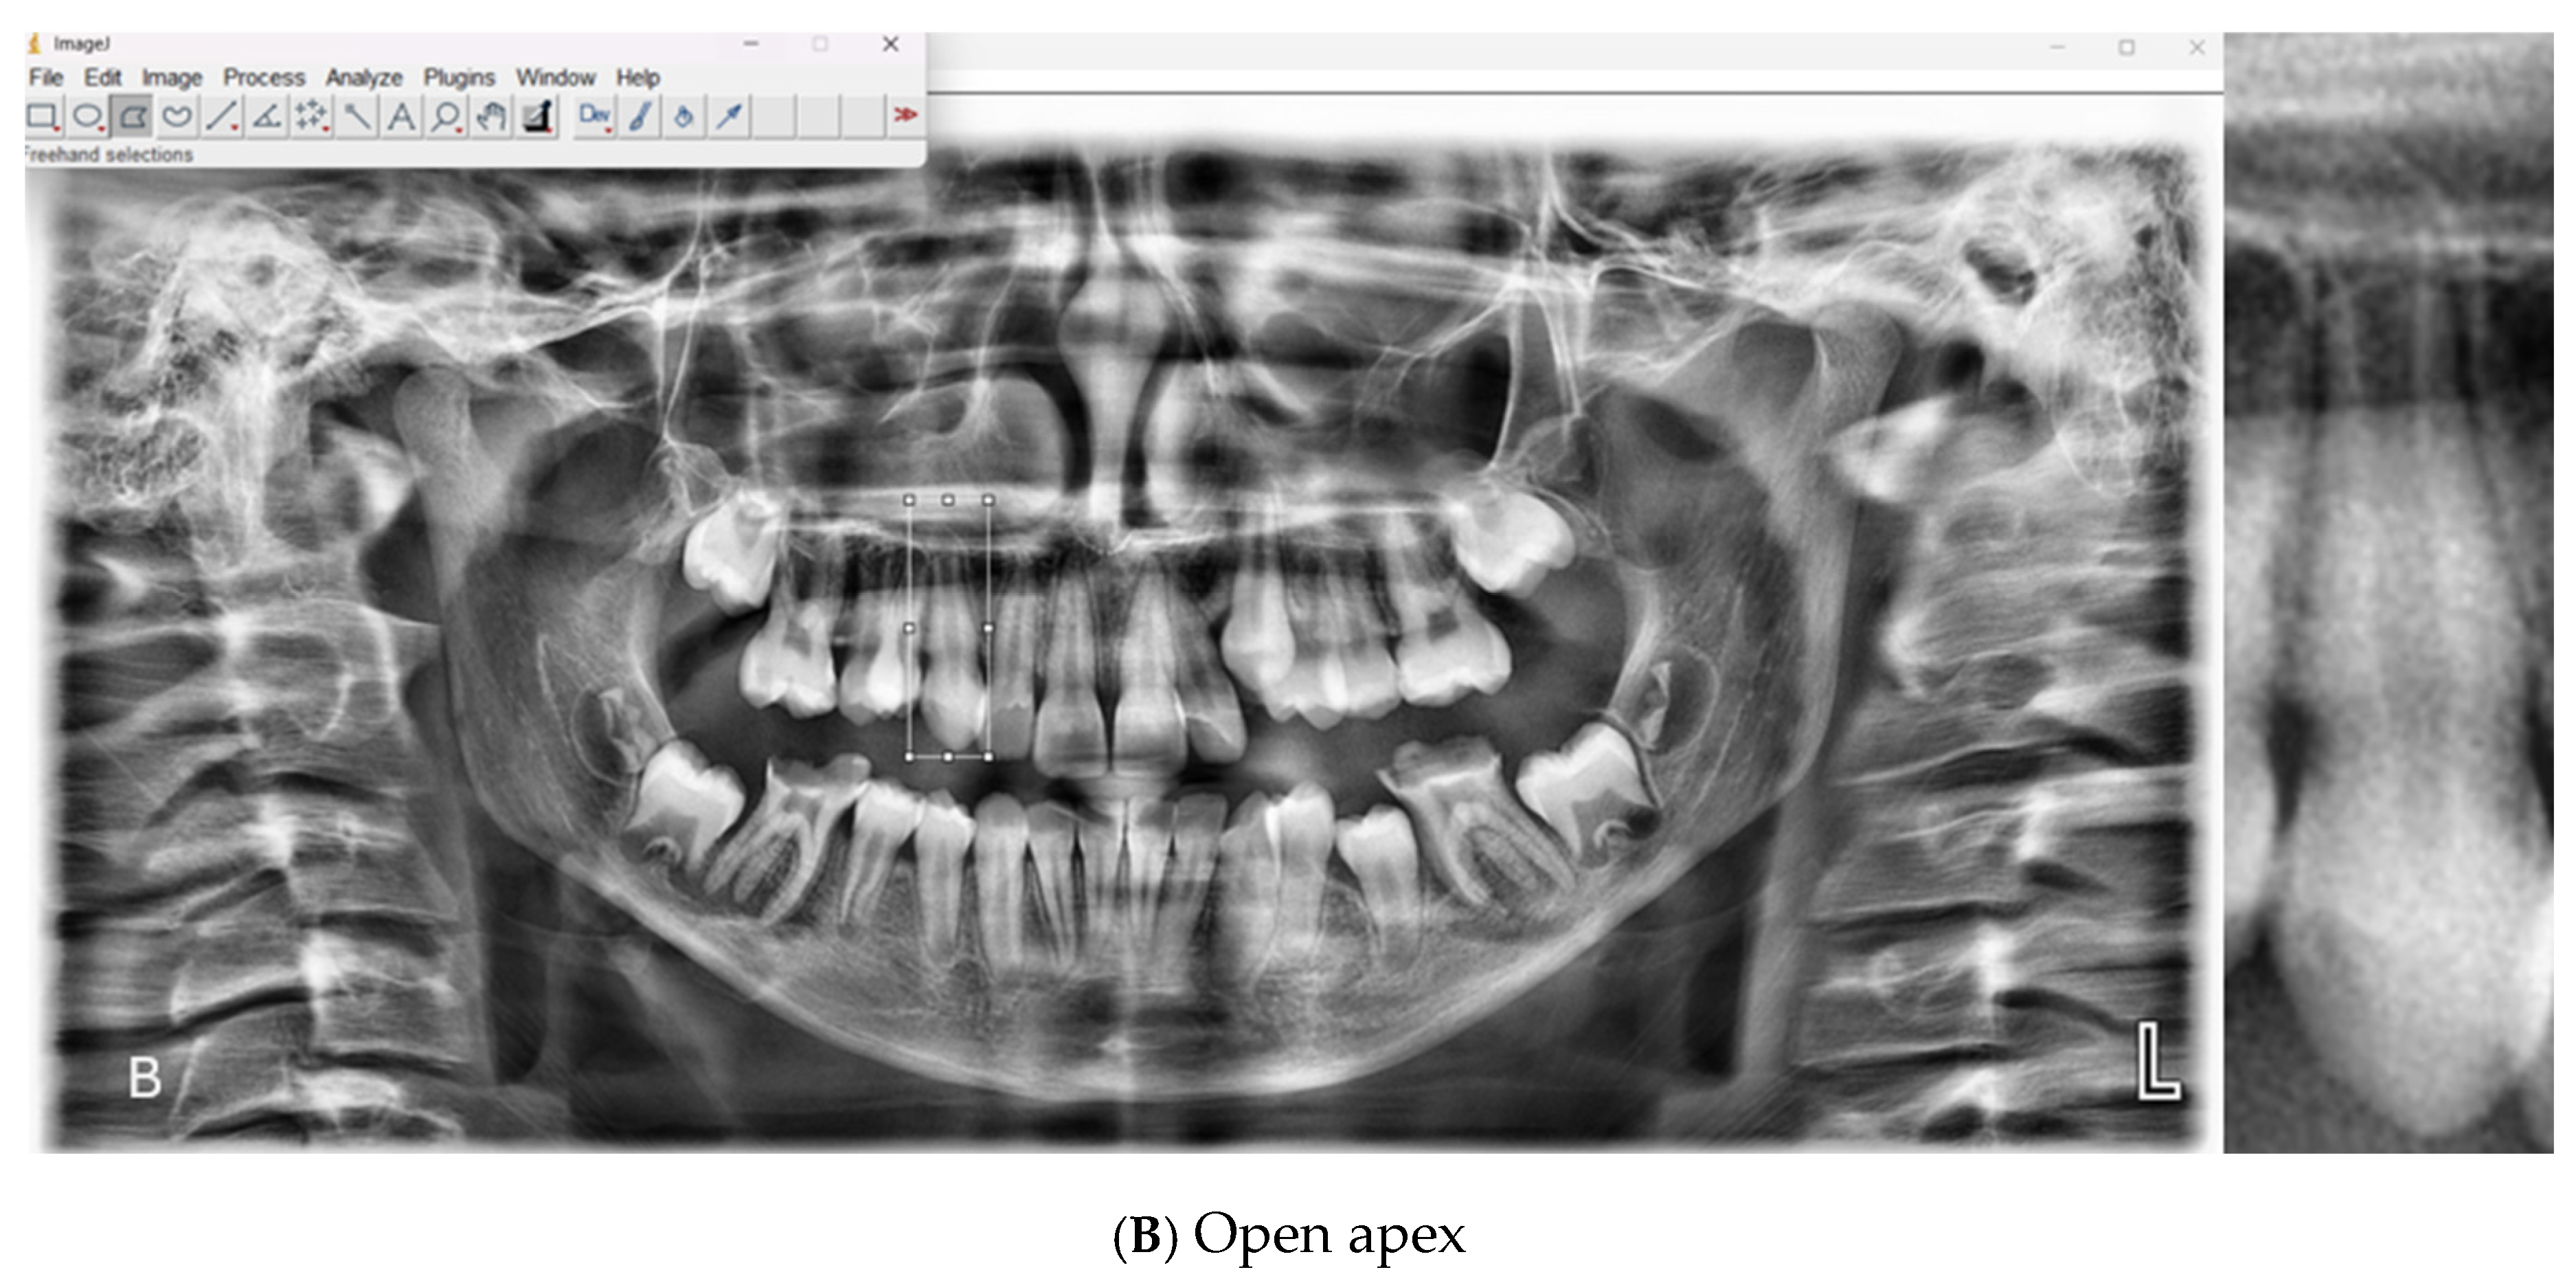

All scans were acquired using a Carestream Dental CS 8100 unit (LLC, 2019) under standard exposure protocols (68 kV, 8 mA, 66 mGy·cm2, 10.8 s). The original images, stored in JPEG format, were processed using ImageJ software (version 1.54g, National Institutes of Health, Bethesda, MD, USA) The apical regions of the relevant teeth were manually isolated, and the regions of interest (ROIs) were saved in PNG format. A total of 1008 ROI images were included in the dataset, consisting of 500 open apex (class 1) and 508 closed apex (class 2) images (Table 1). Representative examples of panoramic radiographs and cropped ROI images used in this study are shown in Figure 1.

Figure 1. Representative panoramic radiographs and cropped regions of interest (ROIs) showing (A) closed apex and (B) open apex teeth.